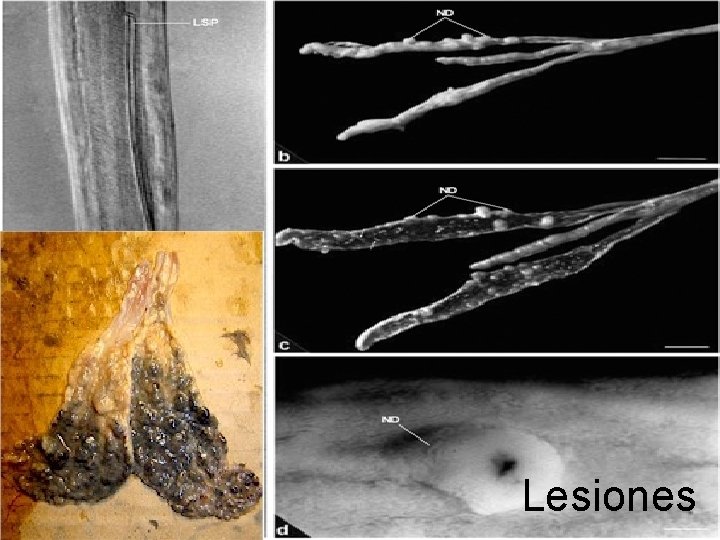

Lesiones